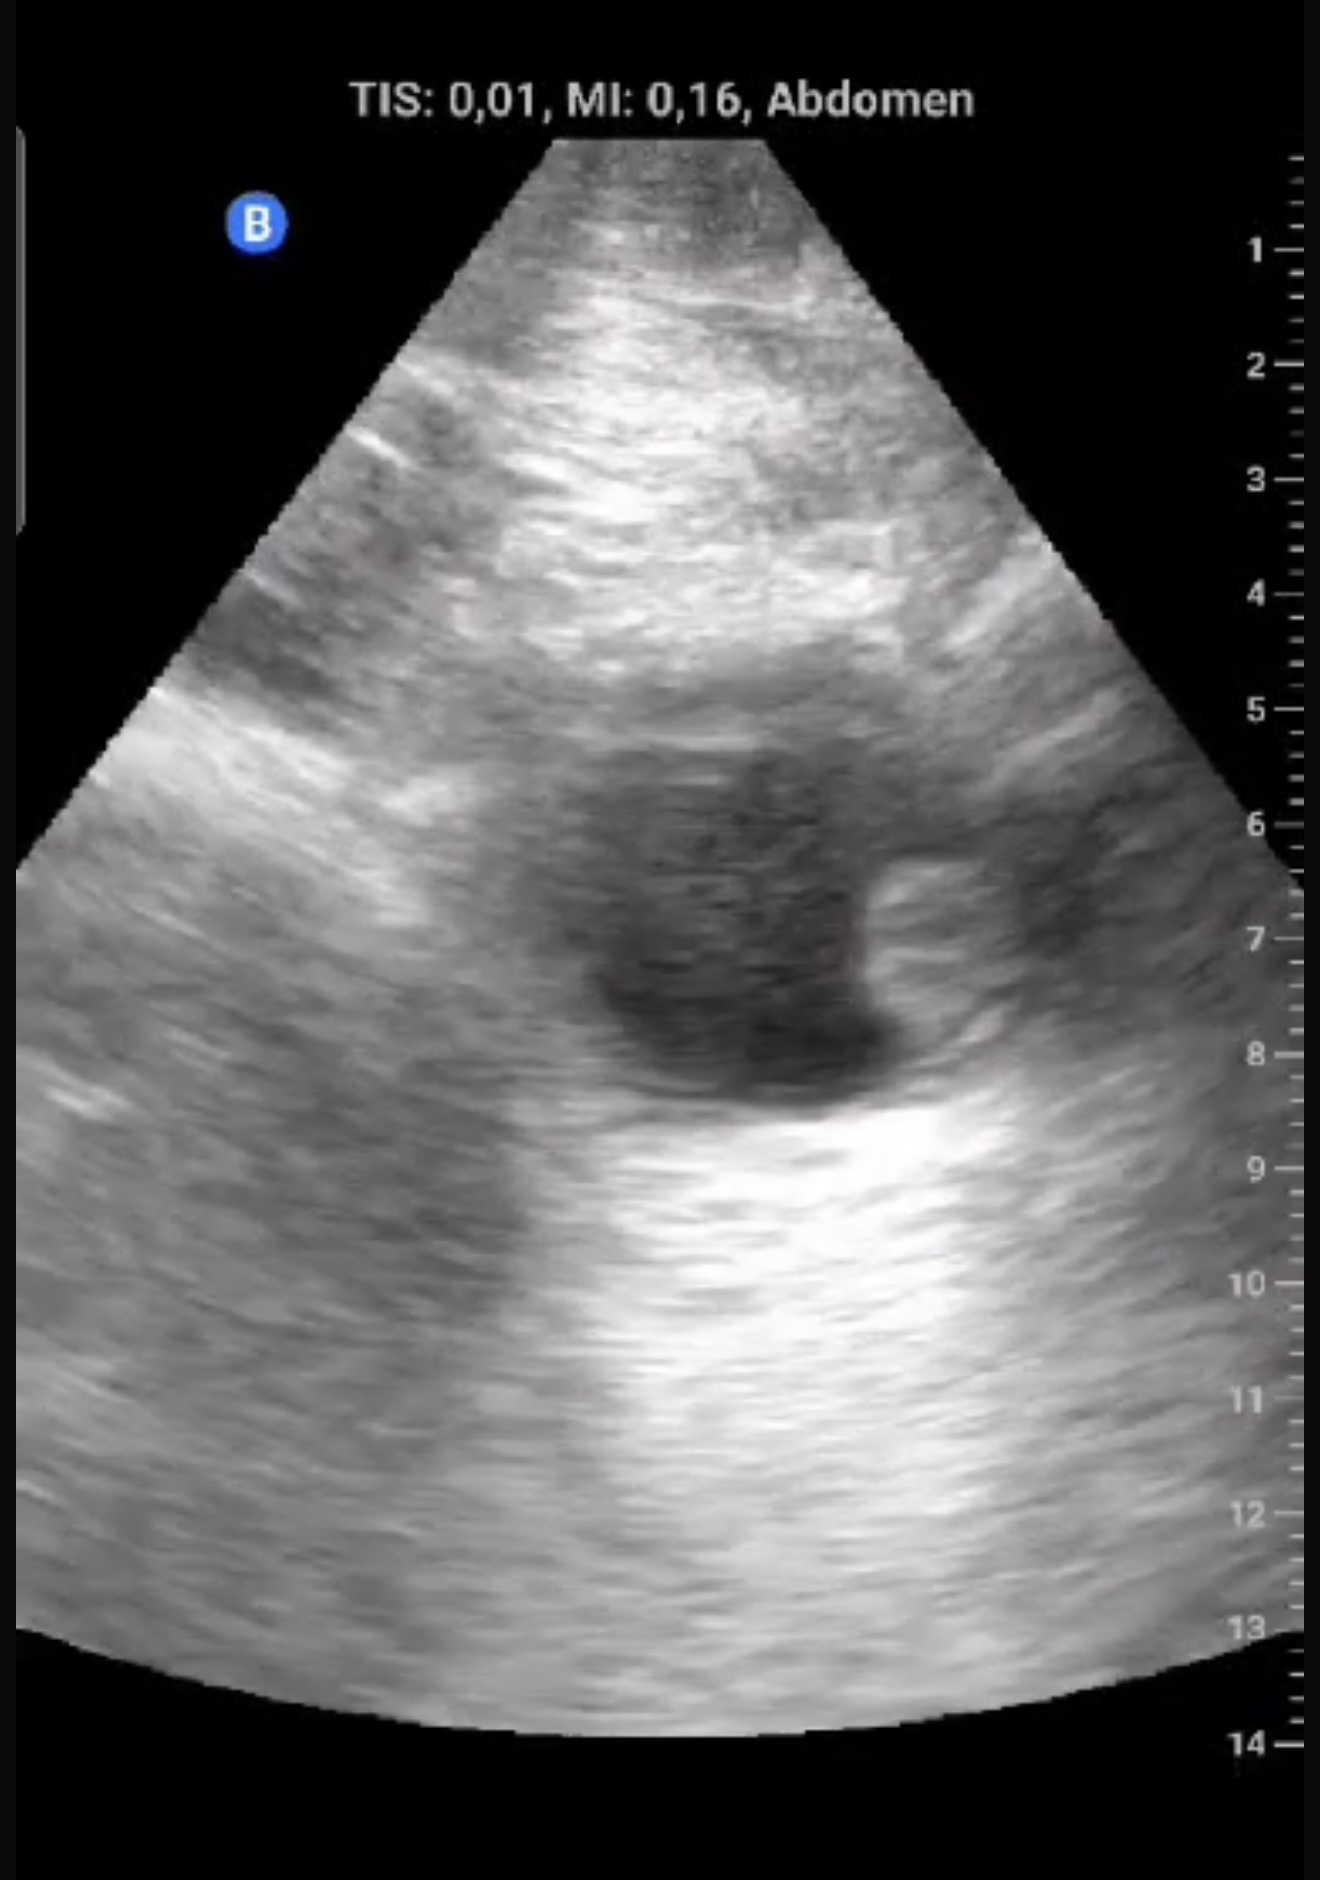

Exfumador, HTA, hipercolesterolemia, cirrosis hepática por alcohol. Hombre de 58 años que refiere episodio de hematuria macroscópica hace dos semanas, coincidiendo con un esfuerzo físico intenso el día previo. No presenta disuria, fiebre, poliaquiuria, ni dolor. En controles posteriores, no había recurrencia de hematuria y el paciente se encontraba asintomático.Exploración física sin hallazgos relevantes. Ecografía realizada en consulta en apenas 5 minutos mostró una masa en la cara lateral izquierda de la vejiga, de 1,5 x 1,3 cm, con características sugerentes de lesión tumoral superficial.

Descripción de los hallazgos ecográficos y las imágenes más relevantes para la resolución del caso

Lesión sólida, pediculada, de bordes definidos y fronda larga en la cara lateral izquierda de la vejiga.

Se sospechó un tumor vesical; pólipo vesical. Urología confirmó la lesión mediante cistoscopia, describiendo una masa papilar superficial de 2 cm en la pared lateral izquierda.